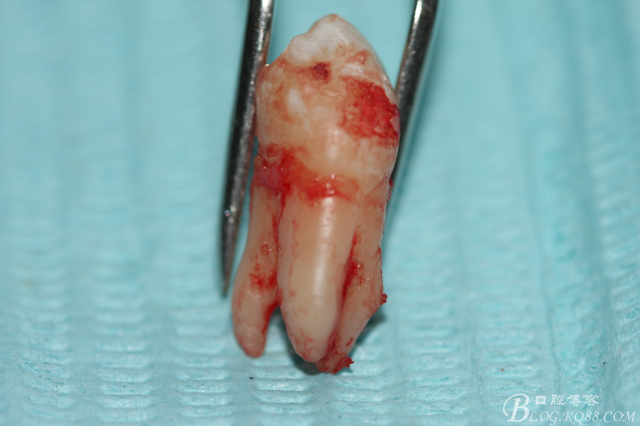

3.術(shù)中拔除上頜第一前磨牙照片

5.上頜離體第一前磨牙牙根形態(tài)